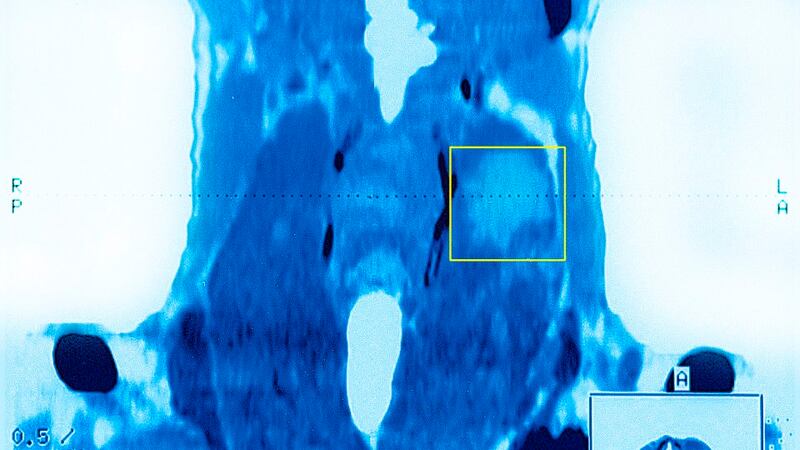

The thyroid gland is a bowtie-shaped gland that lies in the neck wrapped around the windpipe just below the Adam's apple. This gland produces the hormone, thyroxine, which regulates the body's metabolism, affects the heart and respiratory rates, skin maintenance and repair, growth, heat regulation, fertility and digestion.